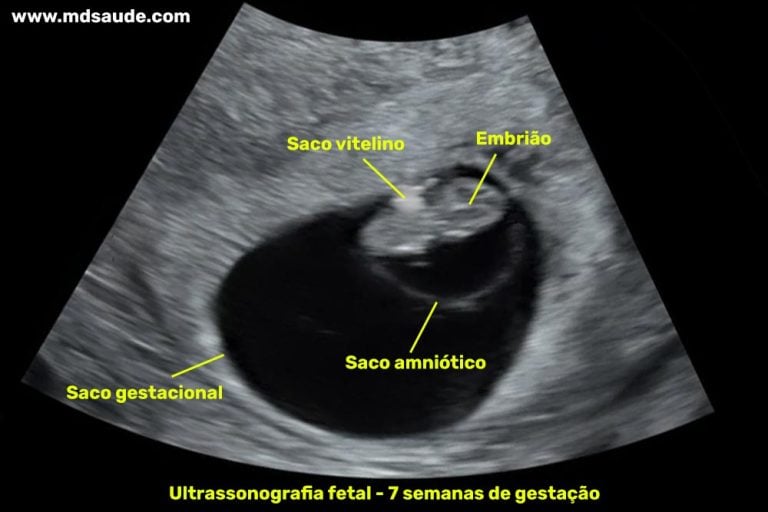

En una ecografía, podrías ver un pequeño bulto con una forma muy incipiente. Será más que una forma en un futuro. La forma se asemeja más a una letra C. Esa forma es el comienzo de su columna vertebral.

Dentro de ese pequeño cuerpo, los órganos están trabajando a toda máquina. El corazón, aunque muy pequeño, ya está latiendo. Puedes verlo latir en una ecografía.